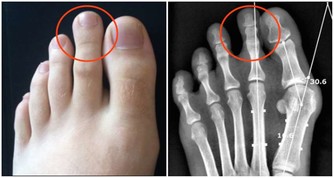

另外,患者也可能存在身體方面的問題,比如運動緩慢或身體僵硬,膀胱或腸道控制喪失(通常在晚期出現),肌肉無力或吞嚥困難。